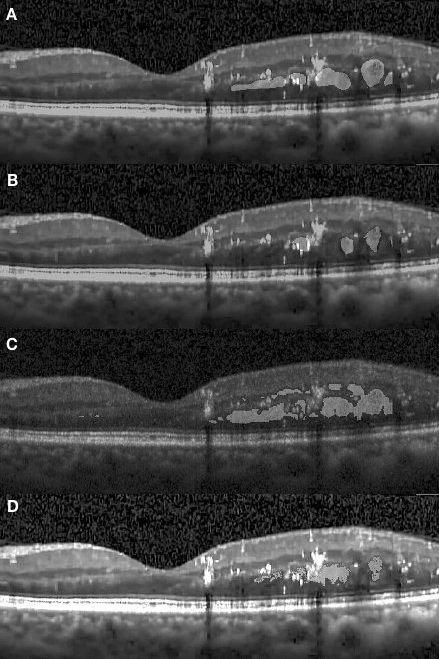

The appearance of fluid edema in OCT images is often shown with a higher contrast against surrounding tissue. Figure 4.1 (A) depicts the foveal region affected with a fluid edema. The dominant edema detaches retinal layers and small edema regions surround it sporadically. It can be seen on the framework results that the boundaries of the dominant edema are accurately segmented out, and the smaller edema on the right-hand side is also segmented individually with clear boundaries. Although two graders annotated the same fluid regions, the framework shows an improvement in terms of boundary recall. A significant inconsistency among manual segmentations on the left side of the fovea has also been observed. Because our network was trained using labels previously provided by the first grader, it is prone to be more similar to their results.

Apart from the segmentation of large areas, there are still some cases where our approach failed to segment the target region accurately. One such event occurred when small target regions were not segmented out, as shown in Fig. 4.1 (D). In this case, the small regions were affected by speckle noise and smoothing effects caused by the pre-processing resulting in the small regions being undetectable by the framework, due to their small initial size leading to them being smoothed out after several pooling layers. In another case, some target regions were only partially segmented, as shown in Fig. 4.4.